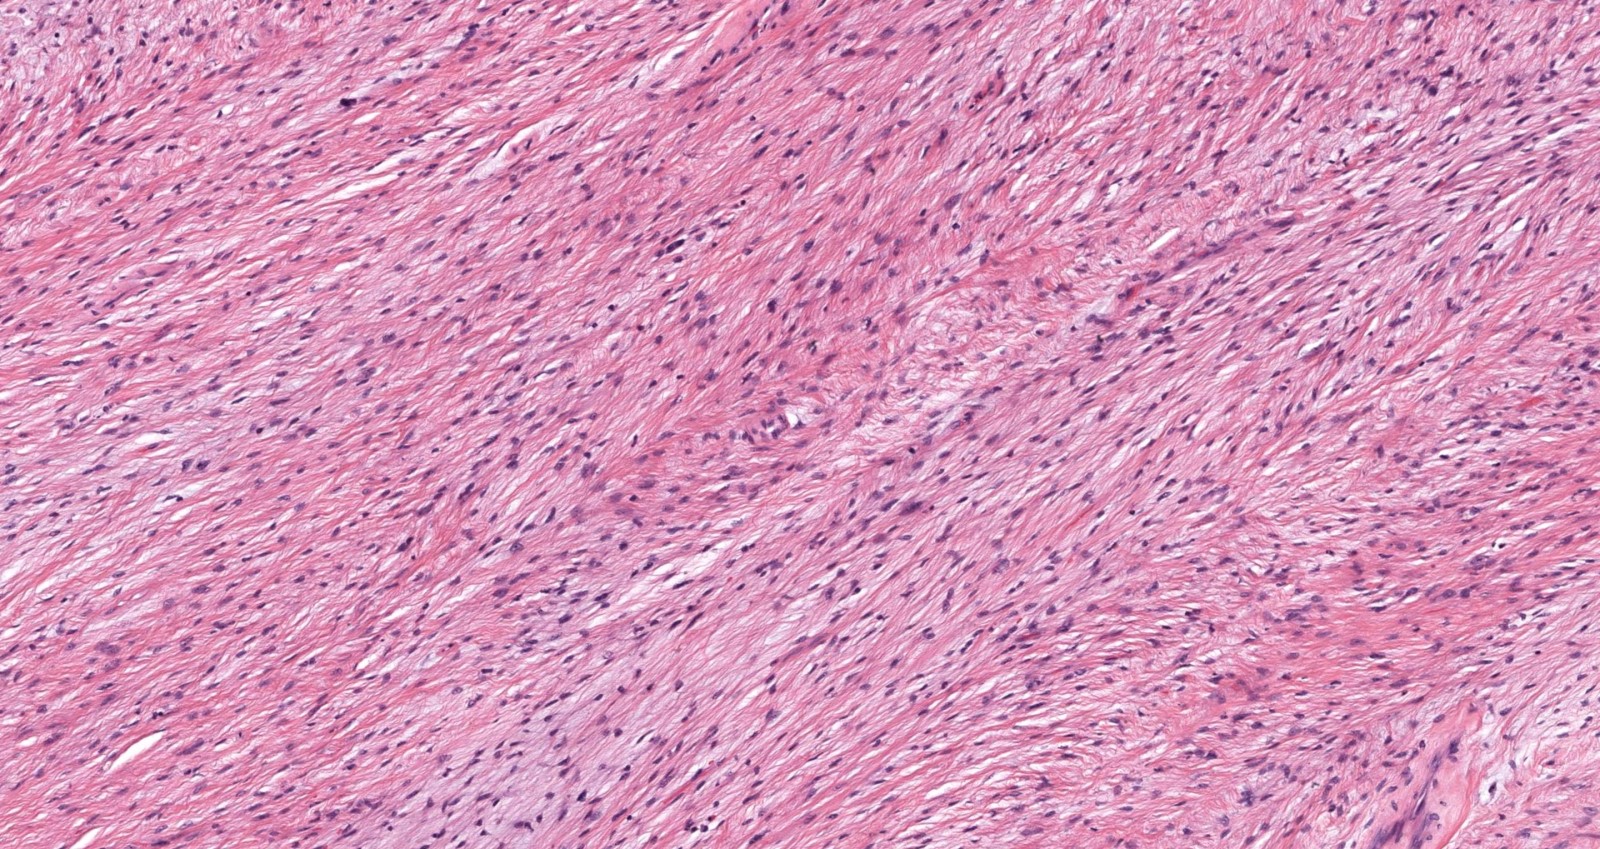

Microscopic (histologic) description

- Low to moderately cellular, bland fusiform or spindled cells with focal to diffuse whirling in heavily collagenized stroma with abrupt transition to myxoid areas

- 45% have epithelioid areas

- Recurrences may show increased cellularity and mitotic activity